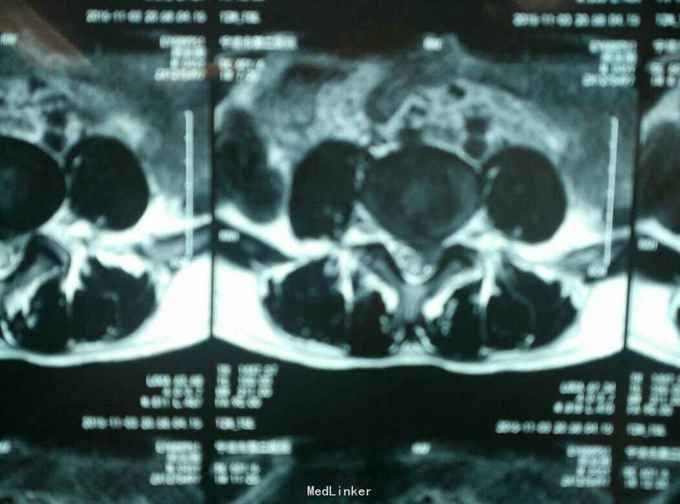

查体:L45间隙压痛,左侧小腿外侧及左足拇趾感觉减退,左下肢肌力四级,左侧下肢直腿抬高试验30度阳性。腰椎MR提示: L4/5椎间盘脱出向上高度游离,压迫左侧神经根。

诊断:L45腰椎间盘脱出游离。 治疗:行侧路椎间孔镜手术。